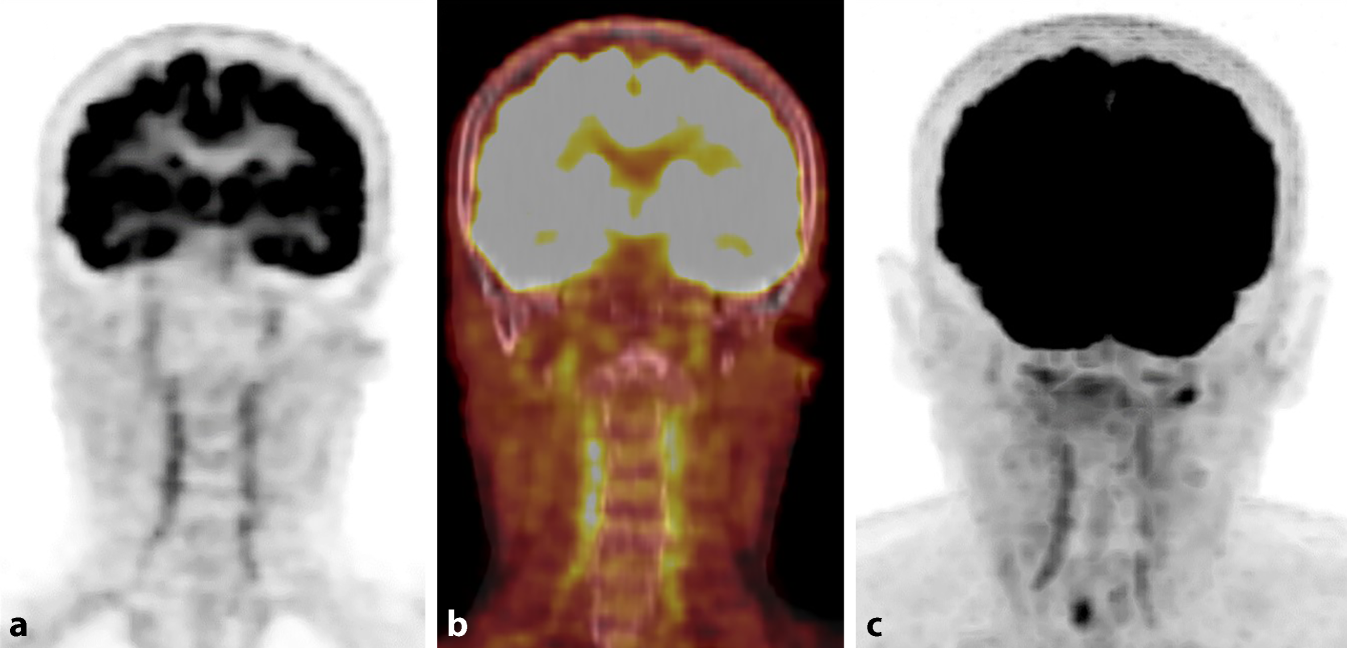

Bei Aufnahme beträgt die Sehschärfe rechts Handbewegungen, bei Entlassung nulla lux. Die Fundoskopie beschreibt eine ödematöse, blasse Papille, eine Tortuositas der Gefäße, eine Ischämiebande der inferioren Hälfte und einen Hemizentralarterienverschluss. CRP und BSG sind bei Aufnahme und im Verlauf normal (Tab. 1). CCT mit Angiographie an Tag 1 ohne Vaskulitis-typische Veränderungen. Die cMRT mit Kontrastmittel (KM) an Tag 3 weist eine Vaskulitis mit Manifestation in den Aa. temporales superficiales nach (Abb. 1). Die rechtsseitige A. temporalis superficialis sowie der Ramus frontalis der kontralateralen Arterie sind verschlossen. Die [18F]-FDG-PET/CT vom selben Tag ergibt Stoffwechselsteigerungen insbesondere in der A. vertebralis beidseits (Abb. 2) sowie geringer in der A. carotis interna, in der Bauchaorta und in den Beinarterien, gut vereinbar mit Riesenzellarteriitis. Eine Temporalisbiopsie wurde von der Patientin abgelehnt.

Abb. 2

a [18F]-FDG-PET, koronar, „standardized uptake value“ (SUV) 7; b [18F]-FDG-PET/CT, koronar, Fusionsbild, SUV 5; c [18F]-FDG-PET, koronar, Maximumintensitätsprojektion (MIP), SUV 7. Deutliche Stoffwechselsteigerung der A. vertebralis beidseits